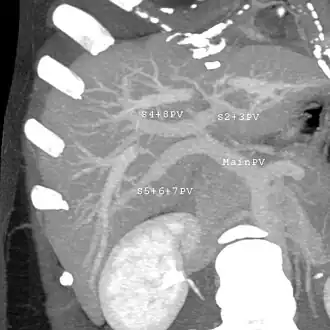

Couinaud classification system

Shape of human liver in animation, with eight Couinaud segments labelled

In the widely used Couinaud system, the functional lobes are further divided into a total of eight subsegments based on a transverse plane through the bifurcation of the main portal vein.[30] The caudate lobe is a separate structure that receives blood flow from both the right- and left-sided vascular branches.[31][32] The Couinaud classification divides the liver into eight functionally independent liver segments. Each segment has its own vascular inflow, outflow and biliary drainage. In the centre of each segment are branches of the portal vein, hepatic artery, and bile duct. In the periphery of each segment is vascular outflow through the hepatic veins.[33] The classification system uses the vascular supply in the liver to separate the functional units (numbered I to VIII) with unit 1, the caudate lobe, receiving its supply from both the right and the left branches of the portal vein. It contains one or more hepatic veins which drain directly into the inferior vena cava.[30] The remainder of the units (II to VIII) are numbered in a clockwise fashion:[33]